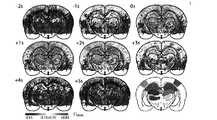

全般に、図4〜13は、覚醒/可動EEG−f超音波手順及び取得プロトコルを示す。 In general, FIGS. 4-13 show awakening / movable EEG-f ultrasound procedures and acquisition protocols.

図4〜8は、外科手順及びプローブ設定を示す。特に、窓境界が、点線で示される。人工頭蓋骨、取付ナット、プローブホルダ、モータ、及びプローブを見ることができる。これらの図はまた、海馬の定位電極及びEEGコネクタを追加した手術結果並びにモータ付並進ステージを備えた動物、並びに人工器官を通した生のmfUSビューを示す。 FIGS. 4-8 show surgical procedures and probe settings. In particular, the window boundaries are indicated by the dotted lines. You can see the artificial skull, mounting nuts, probe holders, motors, and probes. These figures also show the surgical results with the addition of hippocampal stereotaxic electrodes and EEG connectors as well as animals with motorized translational stages, as well as raw mfUS views through artificial organs.

図12及び図13は、発作記録のための「連続モード」取得を示す。 12 and 13 show "continuous mode" acquisition for seizure recording.

自発的な全身性欠神発作は、両側EEGから記録され、f超音波画像トリガマークが、EEGより下に示される。挿入された図に指示される冠状平面は、それぞれ10分間連続して取得される。各々の色は、冠状平面に対応する。 Spontaneous systemic absence seizures are recorded from bilateral EEGs and f ultrasound image trigger marks are shown below the EEGs. The coronal planes indicated in the inserted figure are each acquired continuously for 10 minutes. Each color corresponds to a coronal plane.

各々の図9〜13のために、ベースラインに対する超音波画像の変化が、ボンフェローニ(Bonferroni)補正によりp<10−2の所で示されるパキノス(Paxinos)の地図からの重ね合わせ。For each of Figures 9-13, the change of the ultrasound image with respect to baseline, superposition of map of Pakinosu (Paxinos) shown at p <10-2 by Bonferroni (Bonferroni) correction.

一般に、図14〜20は、自然の事象の循環動態の捕捉を示す。 In general, FIGS. 14-20 show the capture of hemodynamics of natural events.

図14〜16のために、正中線交差上で、様々な時間差(−2〜+5秒)で各々の画素毎のLFPシータ帯域の力と超音波信号との間の迷路実験相互相関(図14参照)を1時間でn=20取得した。広範囲にわたる過潅流が、腹側視床における低潅流と共に、−1秒と+3秒との間で発生した。循環動態信号の領域変動は、地図レイアウト上に指示された画素の空間的平均化によって、得られた(平均+/−sdエンベロープ)。平均シータ力(紫)及び軌道(緑)。縦の点線は、参照正中線交差時間を示す(図15参照)。ピアソンのRの値及びピークの遅延(図16参照)は、左右の背側視床、海馬、及び一次感覚皮質間で近い反応を示す。 For FIGS. 14-16, a labyrinth experiment cross-correlation between the LFP theta band force and the ultrasonic signal for each pixel at various time differences (-2 to +5 seconds) on the median intersection (FIG. 14). (See) was acquired at n = 20 in 1 hour. Extensive hyperperfusion occurred between -1 and +3 seconds, with low perfusion in the subthalamus. The regional variation of the hemodynamic signal was obtained by spatial averaging of the pixels indicated on the map layout (mean +/- sd envelope). Average theta force (purple) and orbit (green). The vertical dotted line indicates the reference midline crossing time (see FIG. 15). Pearson's R value and peak delay (see FIG. 16) show a close response between the left and right dorsal thalamus, hippocampus, and primary sensory cortex.

図17〜20は、連続した冠状平面に対する、時間差0の、mfUS画像と発作との間の癲癇実験相互相関図である(図17参照)。感覚皮質は、一方の半球上でいくらかの過潅流斑を示し、他方の半球上で何も示さなかった。尾側視床もまた、有意に過潅流であった。低潅流は、CPu及びいくつかの皮質部位で見られた。地図レイアウト上に色マークされた部位の平均化は、CPuにおける両側のゆらぎを示した(図18参照)。反対に、発作がEEGに関して両側性である多くの場合で、皮質は過渡的に両側か又は片側の共活性化を示した。発作を起こしている皮質及び視床の同期振動が、尾側平面に見られた(図19参照)。有意な部位の平均は、CPuにおける低潅流及び安定した海馬潅流に対して、感覚皮質及び視床における過潅流を一貫して示した(図20参照)。 FIGS. 17-20 are epilepsy experimental cross-correlation diagrams between mfUS images and seizures with a time difference of 0 for continuous coronal planes (see FIG. 17). The sensory cortex showed some hyperperfusion spots on one hemisphere and nothing on the other hemisphere. The caudal thalamus was also significantly hyperperfused. Hypoperfusion was seen in the CPU and some cortical sites. The averaging of the color-marked parts on the map layout showed fluctuations on both sides in the CPU (see FIG. 18). Conversely, in many cases where the seizures were bilateral with respect to EEG, the cortex showed transient bilateral or unilateral co-activation. Synchronous oscillations of the cortex and thalamus causing seizures were seen in the caudal plane (see Figure 19). Significant site averages consistently showed hyperperfusion in the sensory cortex and thalamus relative to low perfusion and stable hippocampal perfusion in the CPU (see Figure 20).

図14及び図17のために、有意な画素は、ボンフェローニ(Bonferron)補正によりp<10−2で示される。For FIGS. 14 and 17, significant pixels are indicated by p<10 -2 by Bonferroni (Bonferron) correction.